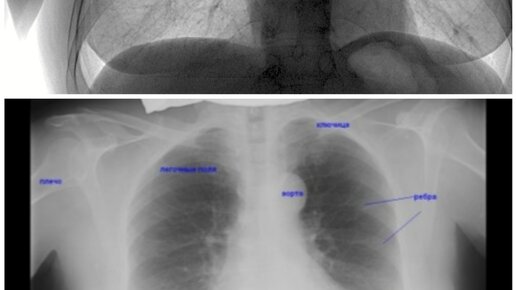

Флюорография: что показывает и как часто можно делать?

Лучи, использующиеся при флюорографии, обладают меньшей жесткостью...